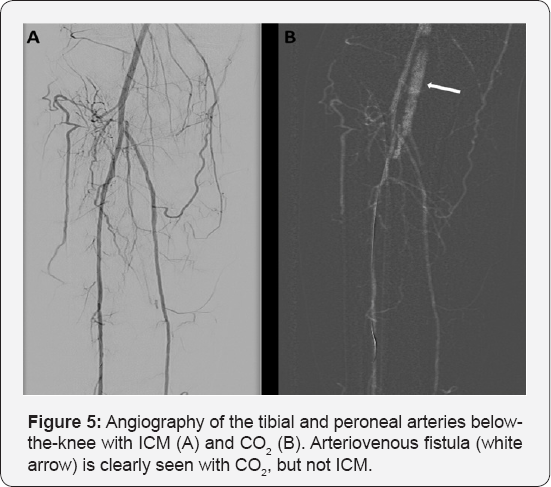

PTA was carried out with CO2 as the contrast agent using the Angiodroid CO2 injector. Left femoral artery was accessed with a 6F Flexor® Ansel guiding sheath (Cook Medical, Bloomington, IN) crossing over to the right femoral artery. Angiography showed occluded right SFA from the ostium. Intravenous fentanyl with a cumulative dose of 100mg was administered for pain relief. The lesion was successfully crossed and predilated with an Armada 5.5x200mm. It was then stented with Supera 5.0x200mm distally and overlapped with Absolute Pro 6.0x80mm proximally up to the SFA ostium. This was followed by post dilatation with Armada 5.0x80mm and 6.0x80mm. Final angiography showed improved flow to the distal vessels (Figure 4). The total ICM used was only 100cc while CO2 volume was 680cc with a total procedural time of 3.5 hours. Serial arterial blood gases (ABG) that were taken demonstrated the absence of CO2 retention. Pre-procedural ABG showed pH 7.48, p CO2 40.4, pO2 87.6, H CO3 29.6, BE 5.7. Post-procedural ABG showed pH 7.43, p CO2 40.4, pO2 89.8, HCO3 26.0, BE 1.6. Renal profile 24 hours after the procedure showed no evidence of contrast-induced nephropathy (CIN). Our experience also showed that smaller vessels (<10mm) had better correlation with ICM than CO2. Many experts opined that it is because CO2 dissolves too quickly and largely due to its low density rather than lack of perfusion (Figure 5) [12]. This case illustrated the feasibility and safety of CO2 in a successful PTA with the use of supplementary ICM.

CO2 DSA has great benefits in a variety of clinical scenarios, specifically CKD andiodinated contrast allergy, which are the bane of ICM. The unique properties of CO2 make it a safe alternative contrast agent in both diagnosis and intervention in this group of patients. Besides peripheral arterial disease, its use in the realm of cardiovascular system has now also expanded into endovascular abdominal aneurysmal repair, venous intervention, transarterial chemo-embolization, vena cava filter placement, renal artery ablation, detection of arteriovenous fistula and diagnosis of acute arterial hemorrhage (2.5 times more sensitive than ICM) [13]. The state-of-the-art Angiodroid technology has revolutionized CO2 DSA and our recent experience with it has witnessed a learning curve that was not at all steep.